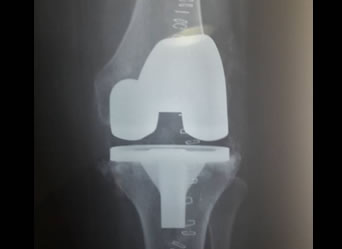

Total Knee Replacement

xray of a successful Total Knee ReplacementIn knee replacement surgery (arthroplasty) a damaged, worn or diseased knee is replaced with an artificial joint. There are two main types of surgery, depending on the condition of the knee: total knee replacement and half (partial) knee replacement. It is an effective procedure that reduces pain and improves quality of life. Materials used for replacing the joint are strong and durable but also optimal for joint function as they produce as little friction as possible.

The artificial joint or prosthesis generally has two components, one made of metal which is usually cobalt -chrome or titanium. The other component is a plastic material called polyethylene. The procedure has been proven to help individuals return back to moderately challenging activities such as golf, bicycling, and swimming. Each operation takes approximately 60-70 minutes to perform. It can be performed with general anaesthesia or regional anaesthesia (spinal or epidural).